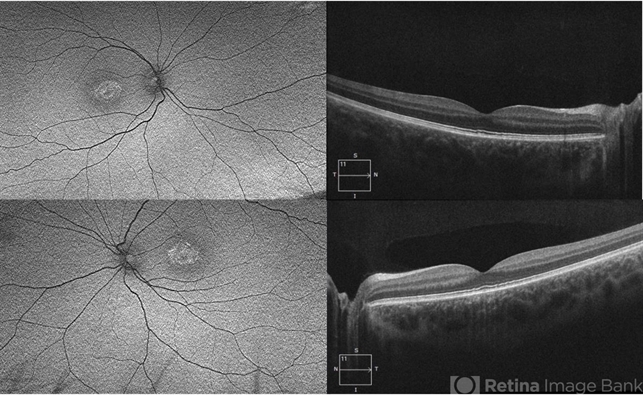

- North Carolina Macular Dystrophy (MCDR1)

- Fundus autofluorescence and OCT photos of a 16 year old female with grade 1 NCMD chr6: 99593030G>T.